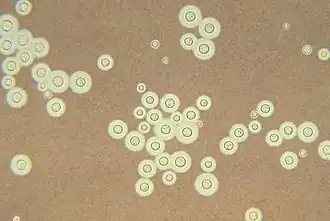

| Yeast state of Cryptococcus neoformans | |

Cryptococcus neoformans typically grows as a yeast (unicellular) and replicates by budding. It makes hyphae during mating, and eventually creates basidiospores at the end of the hyphae before producing spores. Under host-relevant conditions, including low glucose, serum, 5% carbon dioxide, and low iron, among others, the cells produce a characteristic polysaccharide capsule.[8] The recognition of C. neoformans in Gram-stained smears of purulent exudates may be hampered by the presence of the large gelatinous capsule which apparently prevents definitive staining of the yeast-like cells. In such stained preparations, it may appear either as round cells with Gram-positive granular inclusions impressed upon a pale lavender cytoplasmic background or as Gram-negative lipoid bodies.[9] When grown as a yeast, C. neoformans has a prominent capsule composed mostly of polysaccharides. Under the microscope, the India ink stain is used for easy visualization of the capsule in cerebral spinal fluid.[10] The particles of ink pigment do not enter the capsule that surrounds the spherical yeast cell, resulting in a zone of clearance or "halo" around the cells. This allows for quick and easy identification of C. neoformans. Unusual morphological forms are rarely seen.[11] For identification in tissue, mucicarmine stain provides specific staining of polysaccharide cell wall in C. neoformans. Cryptococcal antigen from cerebrospinal fluid is thought to be the best test for diagnosis of cryptococcal meningitis in terms of sensitivity, though it might be unreliable in HIV-positive patients.[12]